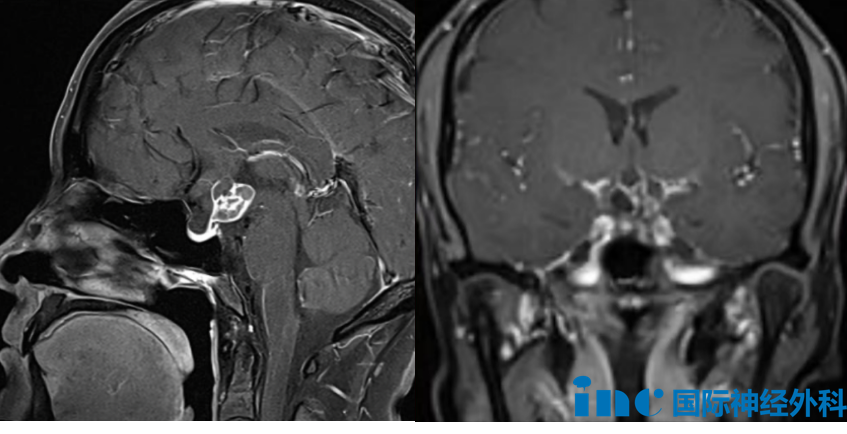

39岁的武女士,因月经停止就诊,检查发现鞍区颅咽管瘤,病灶大小约为一点九厘米×一点八厘米×二点三厘米。这类肿瘤虽然病理上属于良性,复发风险却不容忽视。

颅咽管瘤之所以容易复发,根本原因在于它起源于颅底Rathke囊的鳞状上皮细胞,在脑部中心呈"弥散性"方式生长,与周围丰富的神经和血管结构紧密缠绕,手术难以做到彻底清扫。一旦肿瘤与周边组织粘连严重、甚至出现钙化,手术难度和风险都会显著攀升。保护视神经、下丘脑、周围血管以及垂体柄,是手术必须兼顾的目标,也是最考验术者技术的难点所在。正因如此,初次手术在确保安全的前提下尽量切除肿瘤,意义十分重要。

对于武女士的病情,巴特朗菲教授在术前进行了详细说明:"这枚肿瘤的起源正在垂体柄位置。垂体柄、下丘脑、视神经、视交叉、颈内动脉,这些关键结构彼此之间靠得非常近。垂体腺位于下方,掌控甲状腺及全身各类腺体的分泌;垂体柄则向上与下丘脑相连,精密调节各项生理机能,就如同汽车的刹车与油门,一旦失衡便会出现问题。"所幸武女士就诊较为及时,肿瘤仅约两厘米,是相对适合干预的阶段。